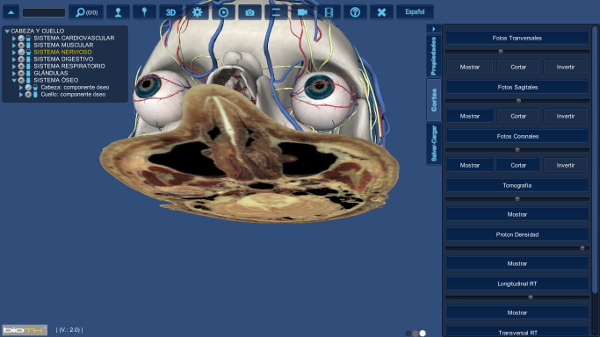

En cualquier momento de una sección de interacción tridimensional es posible definir planos de corte y establecer que órganos serán desactivados a partir del plano | ||

1.Seleccione la pestaña de corte

2.Seleccione el plano de

fotografía en el que desee realizar el corte (Transversal, sagital y/o coronal) , haga clic en el botón mostrar.

3. En

el explorador de órganos seleccione

los órganos o sistemas que desea cortar, haciendo clic en la barra rectangular que se encuentra

al lado izquierdo del nombre del órgano.

La barra se ve en dos colores, indicando cuales órganos o sistemas han sido cortados.

4. Haga clic en el botón cortar de la pestaña de cortes

5.Observe la ventana de

Interacción.

Puede realizar cortes en los

tres ejes anatómicos simultáneamente.

8. Puede cambiar la dirección del

corte al hacer clic en

Para desactivar el corte haga

clic nuevamente en el rectángulo del explorador de órganos.

Para desactivar la fotografía haga clic nuevamente en mostrar en la pestaña de cortes. |